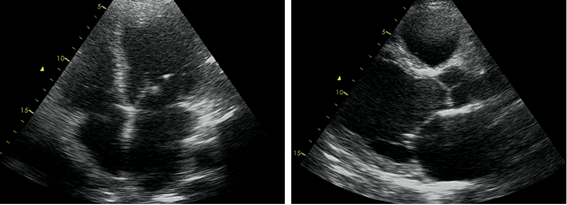

The following year, he was free of dyspnea (NYHA class I/IV), with an improvement of LVEF (45%). A 24h-Holter showed low density PVCs, two episodes of NSVT and a supraventricular extrasystoles burden of 10%, as well as episodes of nocturnal Wenckebach AV block (Figure 1).

Clinical case_ Fig 1 6 The importance of early etiologic diagnosis of dilated cardiomyopathy.png